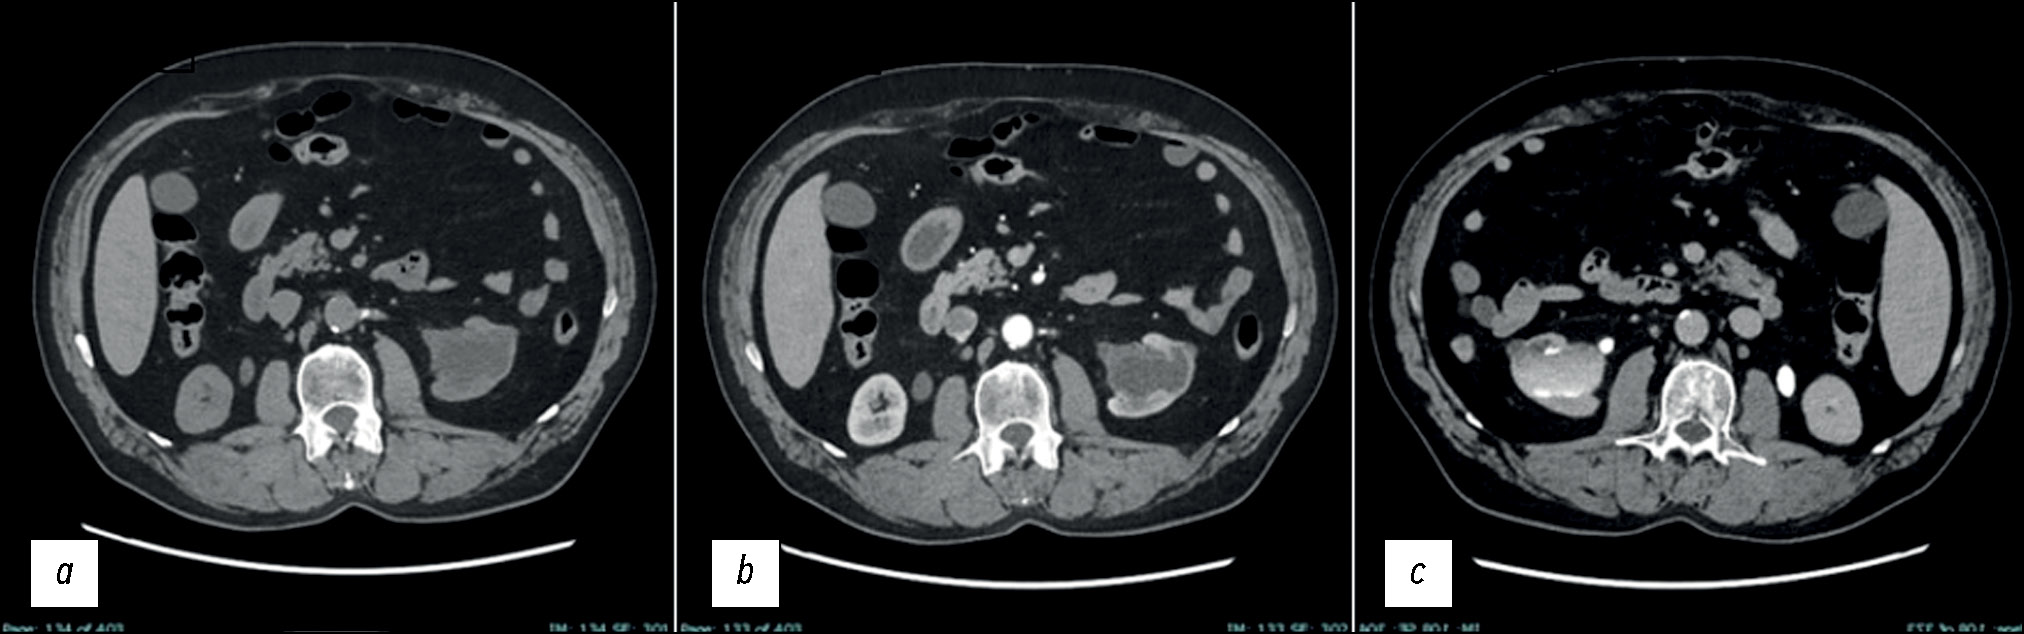

Далее провели КТ-урографию (КТУ). Было подтверждено наличие в средне-нижней части левой почки чётко очерченного дольчатого кистозного образования, сообщающегося с почечной чашечкой, которое характеризовалось пристеночным контрастным усилением в артериальной фазе и постепенно заполнялось контрастным веществом в отсроченной фазе. Камни и гидронефроз отсутствовали. Другие отклонения почек и мочевыводящих путей от нормы также отсутствовали. Обе почки были нормального размера, формы и расположения. Отсутствовали патологическая плотность жировой капсулы, окружающей обе почки, и признаки утолщения околопочечной фасции. На основании морфологических и томоденситометрических характеристик образования первым предполагаемым диагнозом был пиелогенный дивертикул, однако нельзя было исключить и злокачественные новообразования (рис. 2).

Рис. 2. Аксиальные срезы, результаты компьютерной томографической урографии: a — без контрастирования, при сканировании признаки литиаза в обеих почках отсутствовали, образование в левой почке было гиподенсным с томографической плотностью, соответствующей жидкости (в единицах Хаунсфилда); b — в артериальной фазе, при сканировании было отмечено незначительное увеличение плотности кистоподобной полости; c — в экскреторной фазе, при сканировании наблюдалось контрастное усиление стенок полости, с постепенным заполнением полости контрастным веществом.